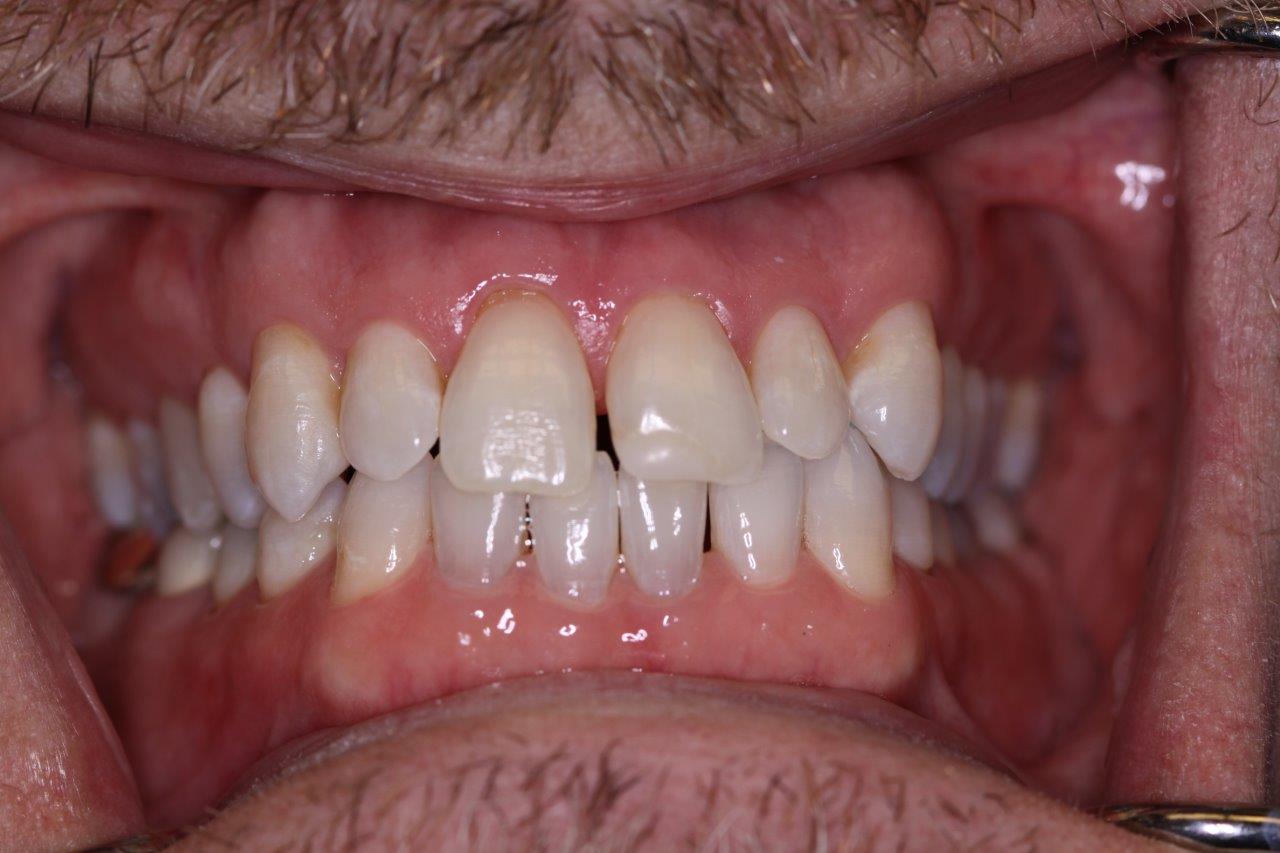

Crown & Veneer

Before